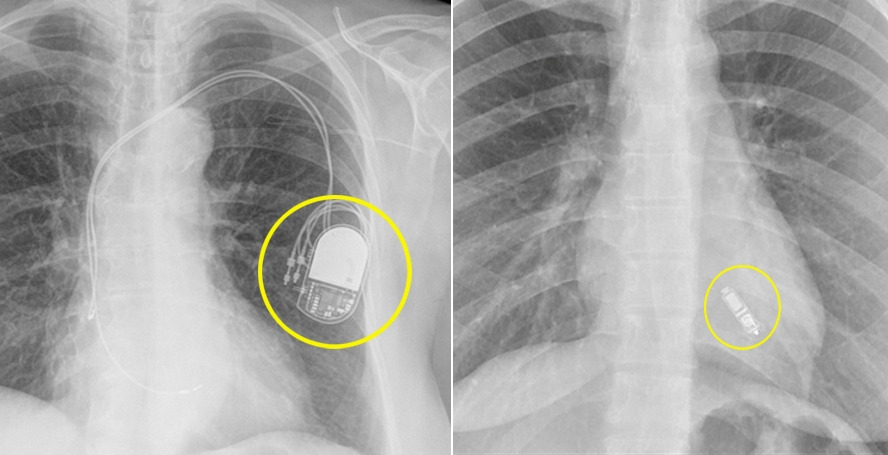

[사진]전극선 없는 무선 심장박동기는 2.6cm 정도의 캡슐 영양제 크기다. 기존 심박동기 부피의 10분의 1정도다. (좌)기존 심장박동기, (우)전극선 없는 무선 심박동기.jpg

이번에 시술한 전극선 없는 무선 심장박동기는 2.6cm 정도의 캡슐 영양제 크기다. 기존 심박동기 부피의 10분의 1 정도다. 쇄골하정맥이 좁아도 시술이 가능하다. 심박동기 크기가 작아 가슴 피부를 절개하지 않고, 허벅지 쪽 대퇴정맥을 통해 심장(우심실)에 삽입한다. 삽입 후 10년 정도 배터리로 작동되며, 심박동기를 제거할 필요 없이 새로 박동기를 삽입할 수 있다. 전극선 교체도 필요 없어 다시 피부를 절개하지 않아도 된다. 또 절개 부위가 작아 시술 시간 짧고 통증이나 출혈, 혈종 등의 부작용 발생 위험이 줄어 환자 회복도 빠르다.